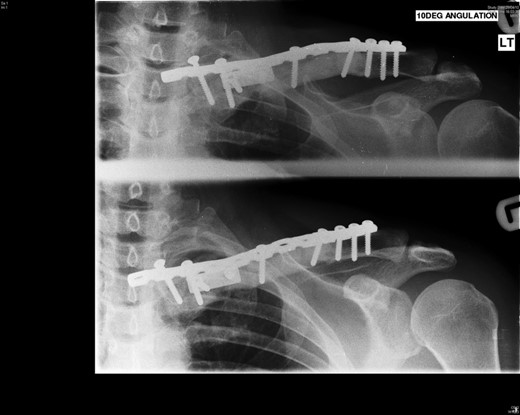

The patient had 3 monthly follow-up and at 2 years, there was no evidence of local recurrence or complications. She had a full and pain-free range of motion of the shoulder and was completely asymptomatic (Fig. 4).

Four years following the procedure, after discomfort in her shoulder, X-rays revealed that the plate had broken and there was a fracture of the clavicle. This plate was subsequently removed and an underlying non-union was found, but no evidence of recurrence of the tumour. She has been managed symptomatically since and has a full range of shoulder movements but some discomfort when doing heavy lifting, which she therefore avoids (Figs 5 and 6).